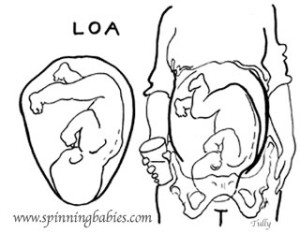

You will hear your doctor state your baby’s position and that will usually consist of 3 letters, but what do they mean? Let’s try to break this down!

L or R

Meaning Left (L) or Right (R) and referring to which side of your uterus your baby’s back is up against.

O

Meaning Occiput (O) and referring to the back of your baby’s head.

A, P, or T

Meaning Anterior (A) referring to your back, near the pubic bone, Posterior (P) referring to your front, near the abdomen or Transverse (T) referring to halfway between Anterior and Posterior.

LOA or ROA

Left Occiput Anterior or Right Occiput Anterior.

The Left Occiput Anterior (LOA) is known as the most optimal position for birth because it is one of the positions to help baby be in the smallest diameter to fit the pelvis. The crown of the LOA baby’s head most often enters the pelvis first, tucking the chin which helps the baby fit in a way that the baby’s head can mold/shape most effectively. The baby’s back can curve most effectively in this position as well. The baby slides down the softening abdomen to enter the brim. (https://www.spinningbabies.com)